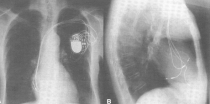

Although often fiddly we regard pacemaker implantation as a minor proceure and it should not take more than an hour or two

Defibrillators (ICDs) are useful in people who seem to be at risk from a life threatening arrhythmia. The device works as a pacemaker if required but can also deliver a shock to the heart if the rhythm should degenerate, restoring normal rhythm.

ICDs are implanted both for those who have suffered a serious arrhythmia and recovered and for those who seem to be at risk of serious arrhythmias in the future.